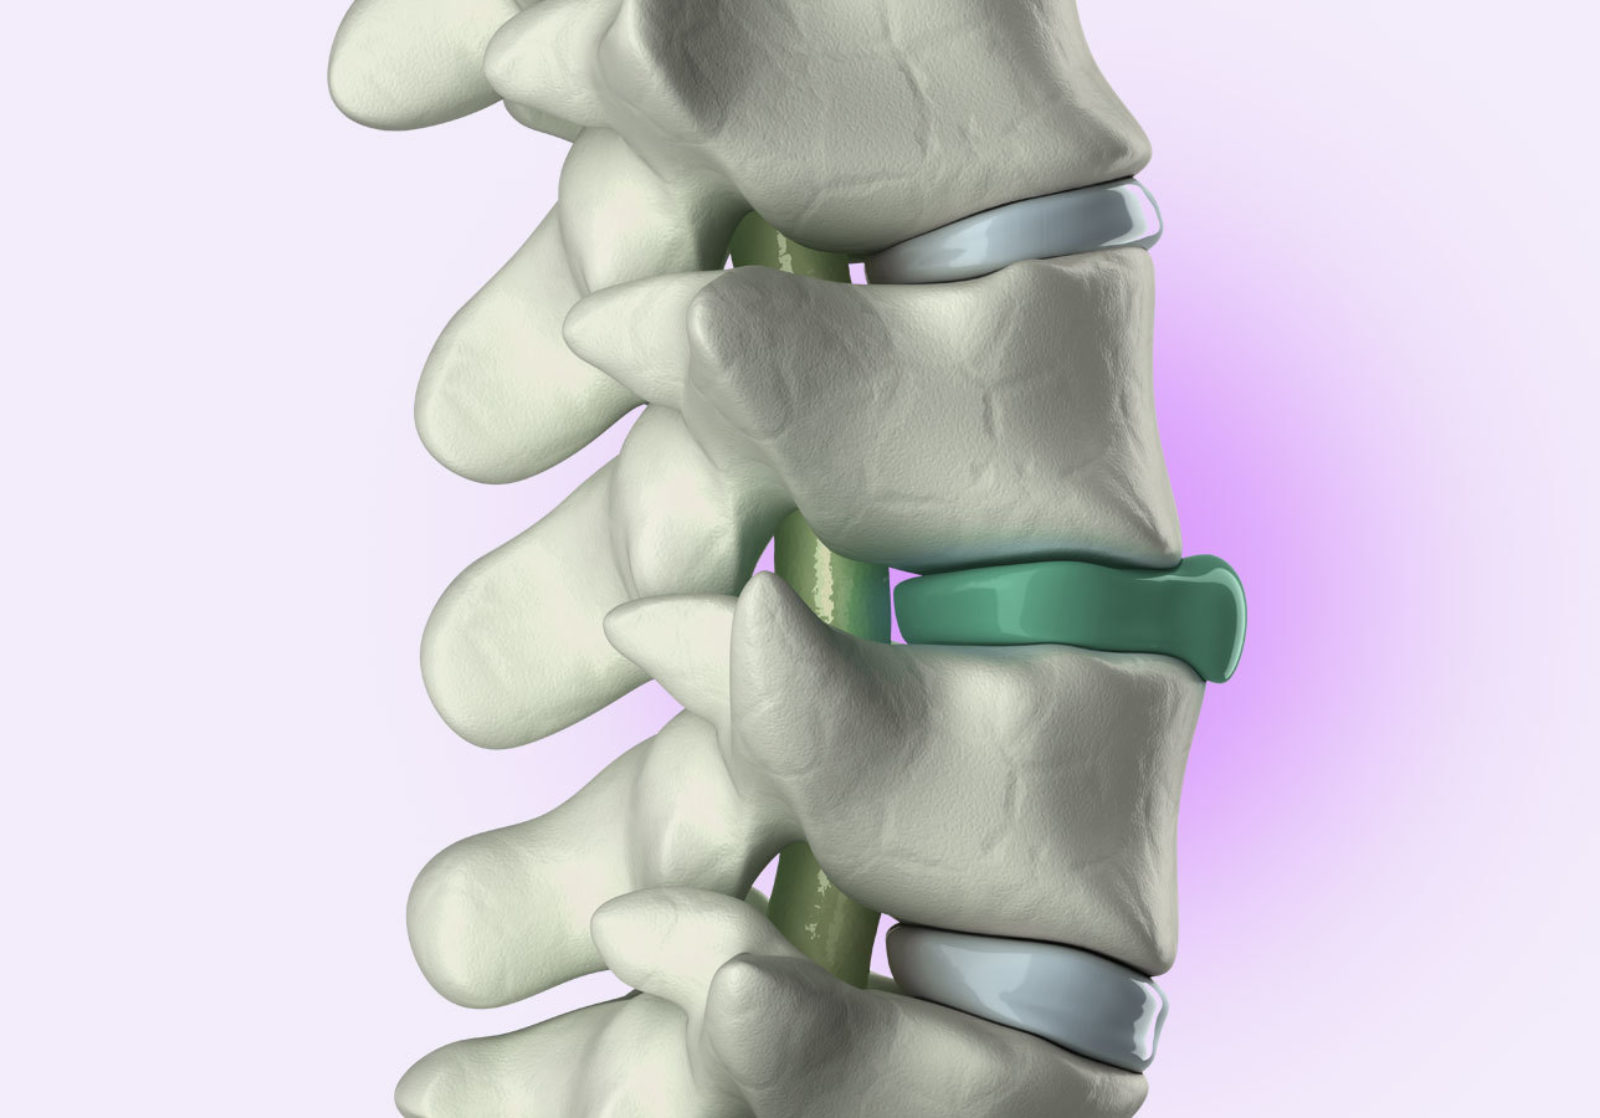

- Diagnostizierte Beschwerdebilder (z.B. Bandscheibenvorfall, Skoliose, etc.)

Meistens suchen Menschen mit körperlichen Beschwerden nach einer speziellen Art von Matratze, um die Probleme zu verbessern. Viele suchen eine Lösung bei Bandscheibenvorfällen oder anderen Rückenschmerzen. Neben Bewegung und einer klassischen Therapie kann hier die Matratze eine wesentliche Verbesserung bringen. Immerhin verbringen wir Menschen ca. 6-8 Stunden pro Tag auf der Matratze. Grundsätzlich lässt sich durch eine gute Nachtlagerung fast jedes Problem verbessern, immerhin liegt in der Nachtruhe ein großer Teil des regenerativen Potentials. Wenn also körperliche Beschwerden vorhanden sind, ist die Auseinandersetzung mit der eigenen Matratze unausweichlich, immerhin ist sie das Produkt, welches im Alltag am meisten genutzt wird.